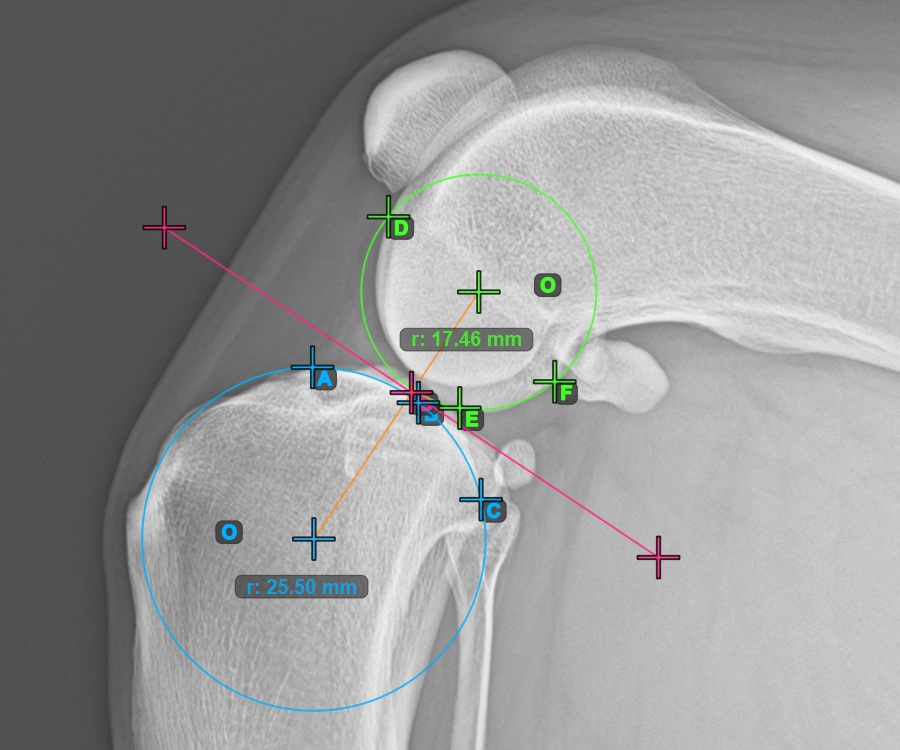

Kezdje el a mérést a három pont megjelölésével a Condylus Medialis Tibialis-on.

Jelölje meg a három pontot a tibia fő condylusán (Medialis Tibialis). A sorrendtől függetlenül ügyeljen arra, hogy megjelölje a legfelső pontot, a legalacsonyabb pontot és a Medialis Tibialis középpontját. A három pont alapján a rendszer automatikusan létrehoz egy kört.

A lenti kép a Condylus Medialis Tibialis-on elhelyezett három pont tipikus elhelyezkedését ábrázolja.